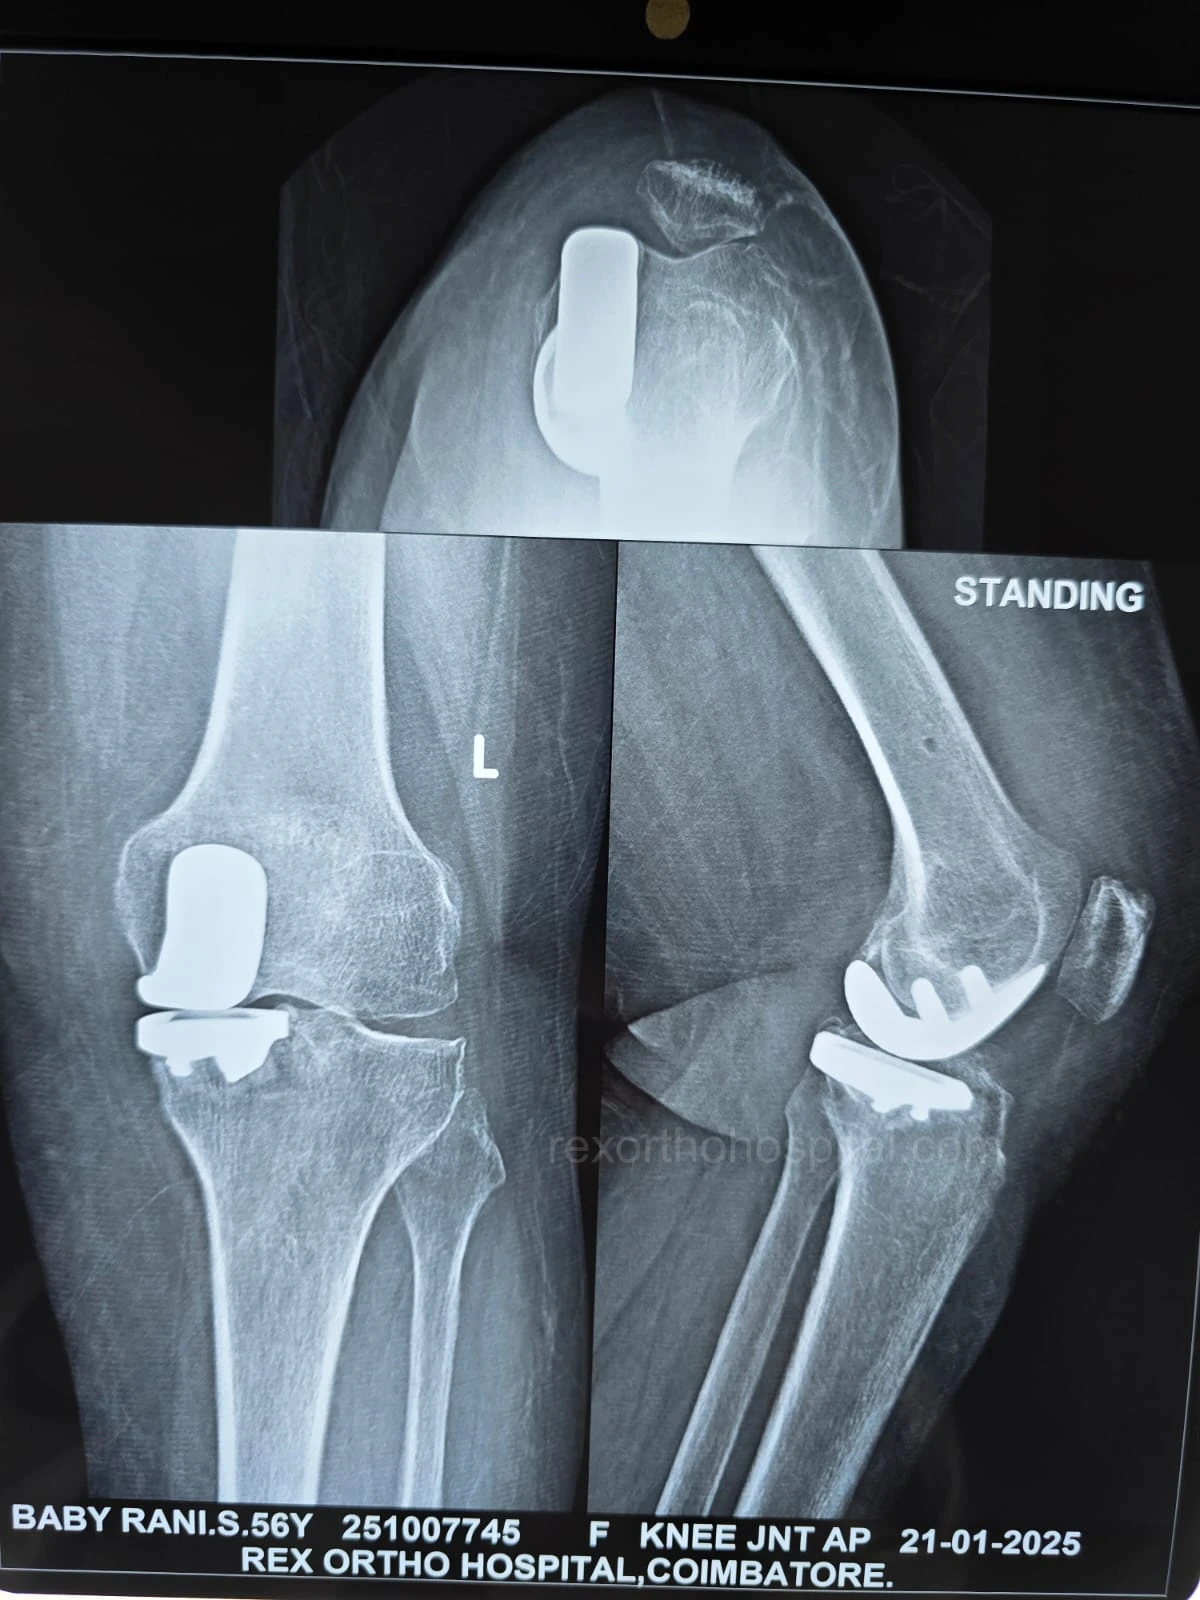

Elbow stiffness treatment aims to restore smooth movement and reduce pain caused by injury, arthritis, or long-term immobility. Our approach improves flexibility and helps regain everyday function.

From diagnosis to surgery and recovery, our team ensures you receive expert treatment and individual attention throughout your treatment journey